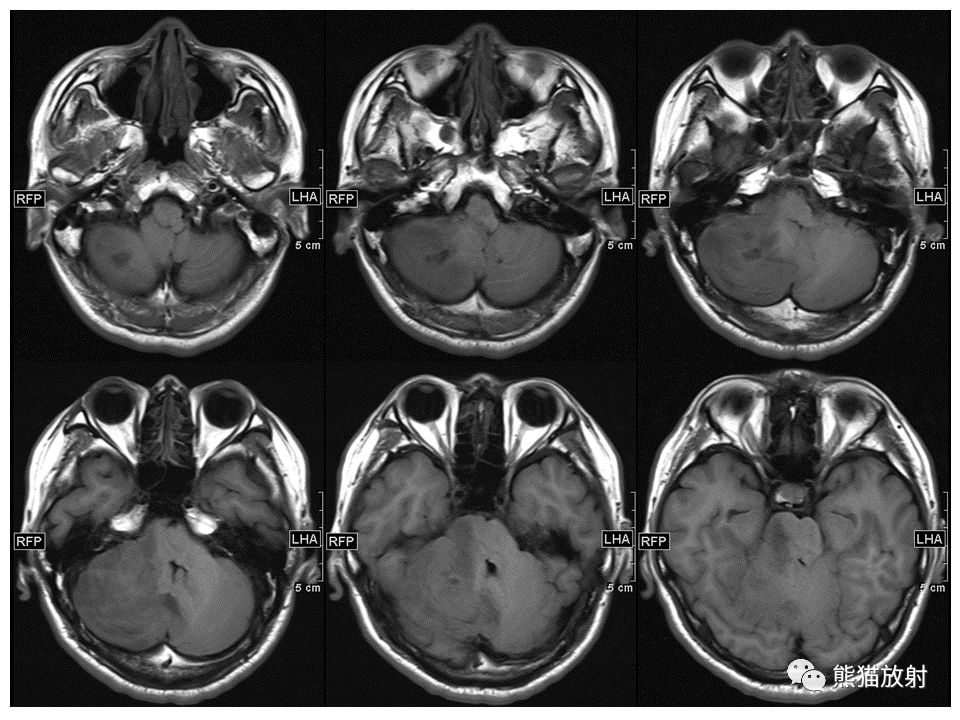

【PPT】小脑发育不良性神经节细胞瘤 VS 成人型髓母细胞瘤-3